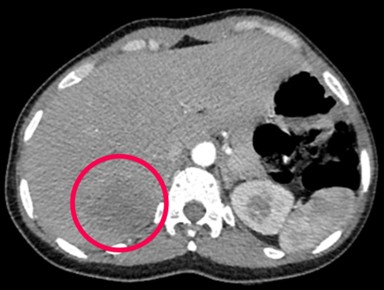

Làm các xét nghiệm khác tầm soát toàn thân phát hiện thêm các tổn thương tại gan và xương cánh chậu 2 bên.

Hình 5: Tổn thương gan trước điều trị: khối giảm tỷ trọng ở hạ phân thùy S7, kích thước 37x45mm, ngấm thuốc kém sau tiêm.